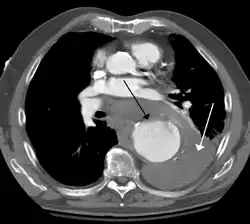

A thoracic aortic aneurysm is an aortic aneurysm that presents primarily in the thorax.

A thoracic aortic aneurysm is the "ballooning" of the upper aspect of the aorta, above the diaphragm. Untreated or unrecognized they can be fatal due to dissection or "popping" of the aneurysm leading to nearly instant death. Thoracic aneurysms are less common than an abdominal aortic aneurysm.[2] However, a syphilitic aneurysm is more likely to be a thoracic aortic aneurysm than an abdominal aortic aneurysm. This condition is commonly treated via a specialized multidisciplinary approach with both vascular surgeons and cardiac surgeons.

Diagnosis

Thoracic aortic aneurysm is defined as a cross-sectional diameter exceeding the following cutoff:

- 4.5 cm in the United States[7]

- 4.0 cm in South Korea[8]

A diameter of 3.5 cm is generally considered dilated.[7] However, average values vary with age and size of the reference population, as well as different segments of the aorta.